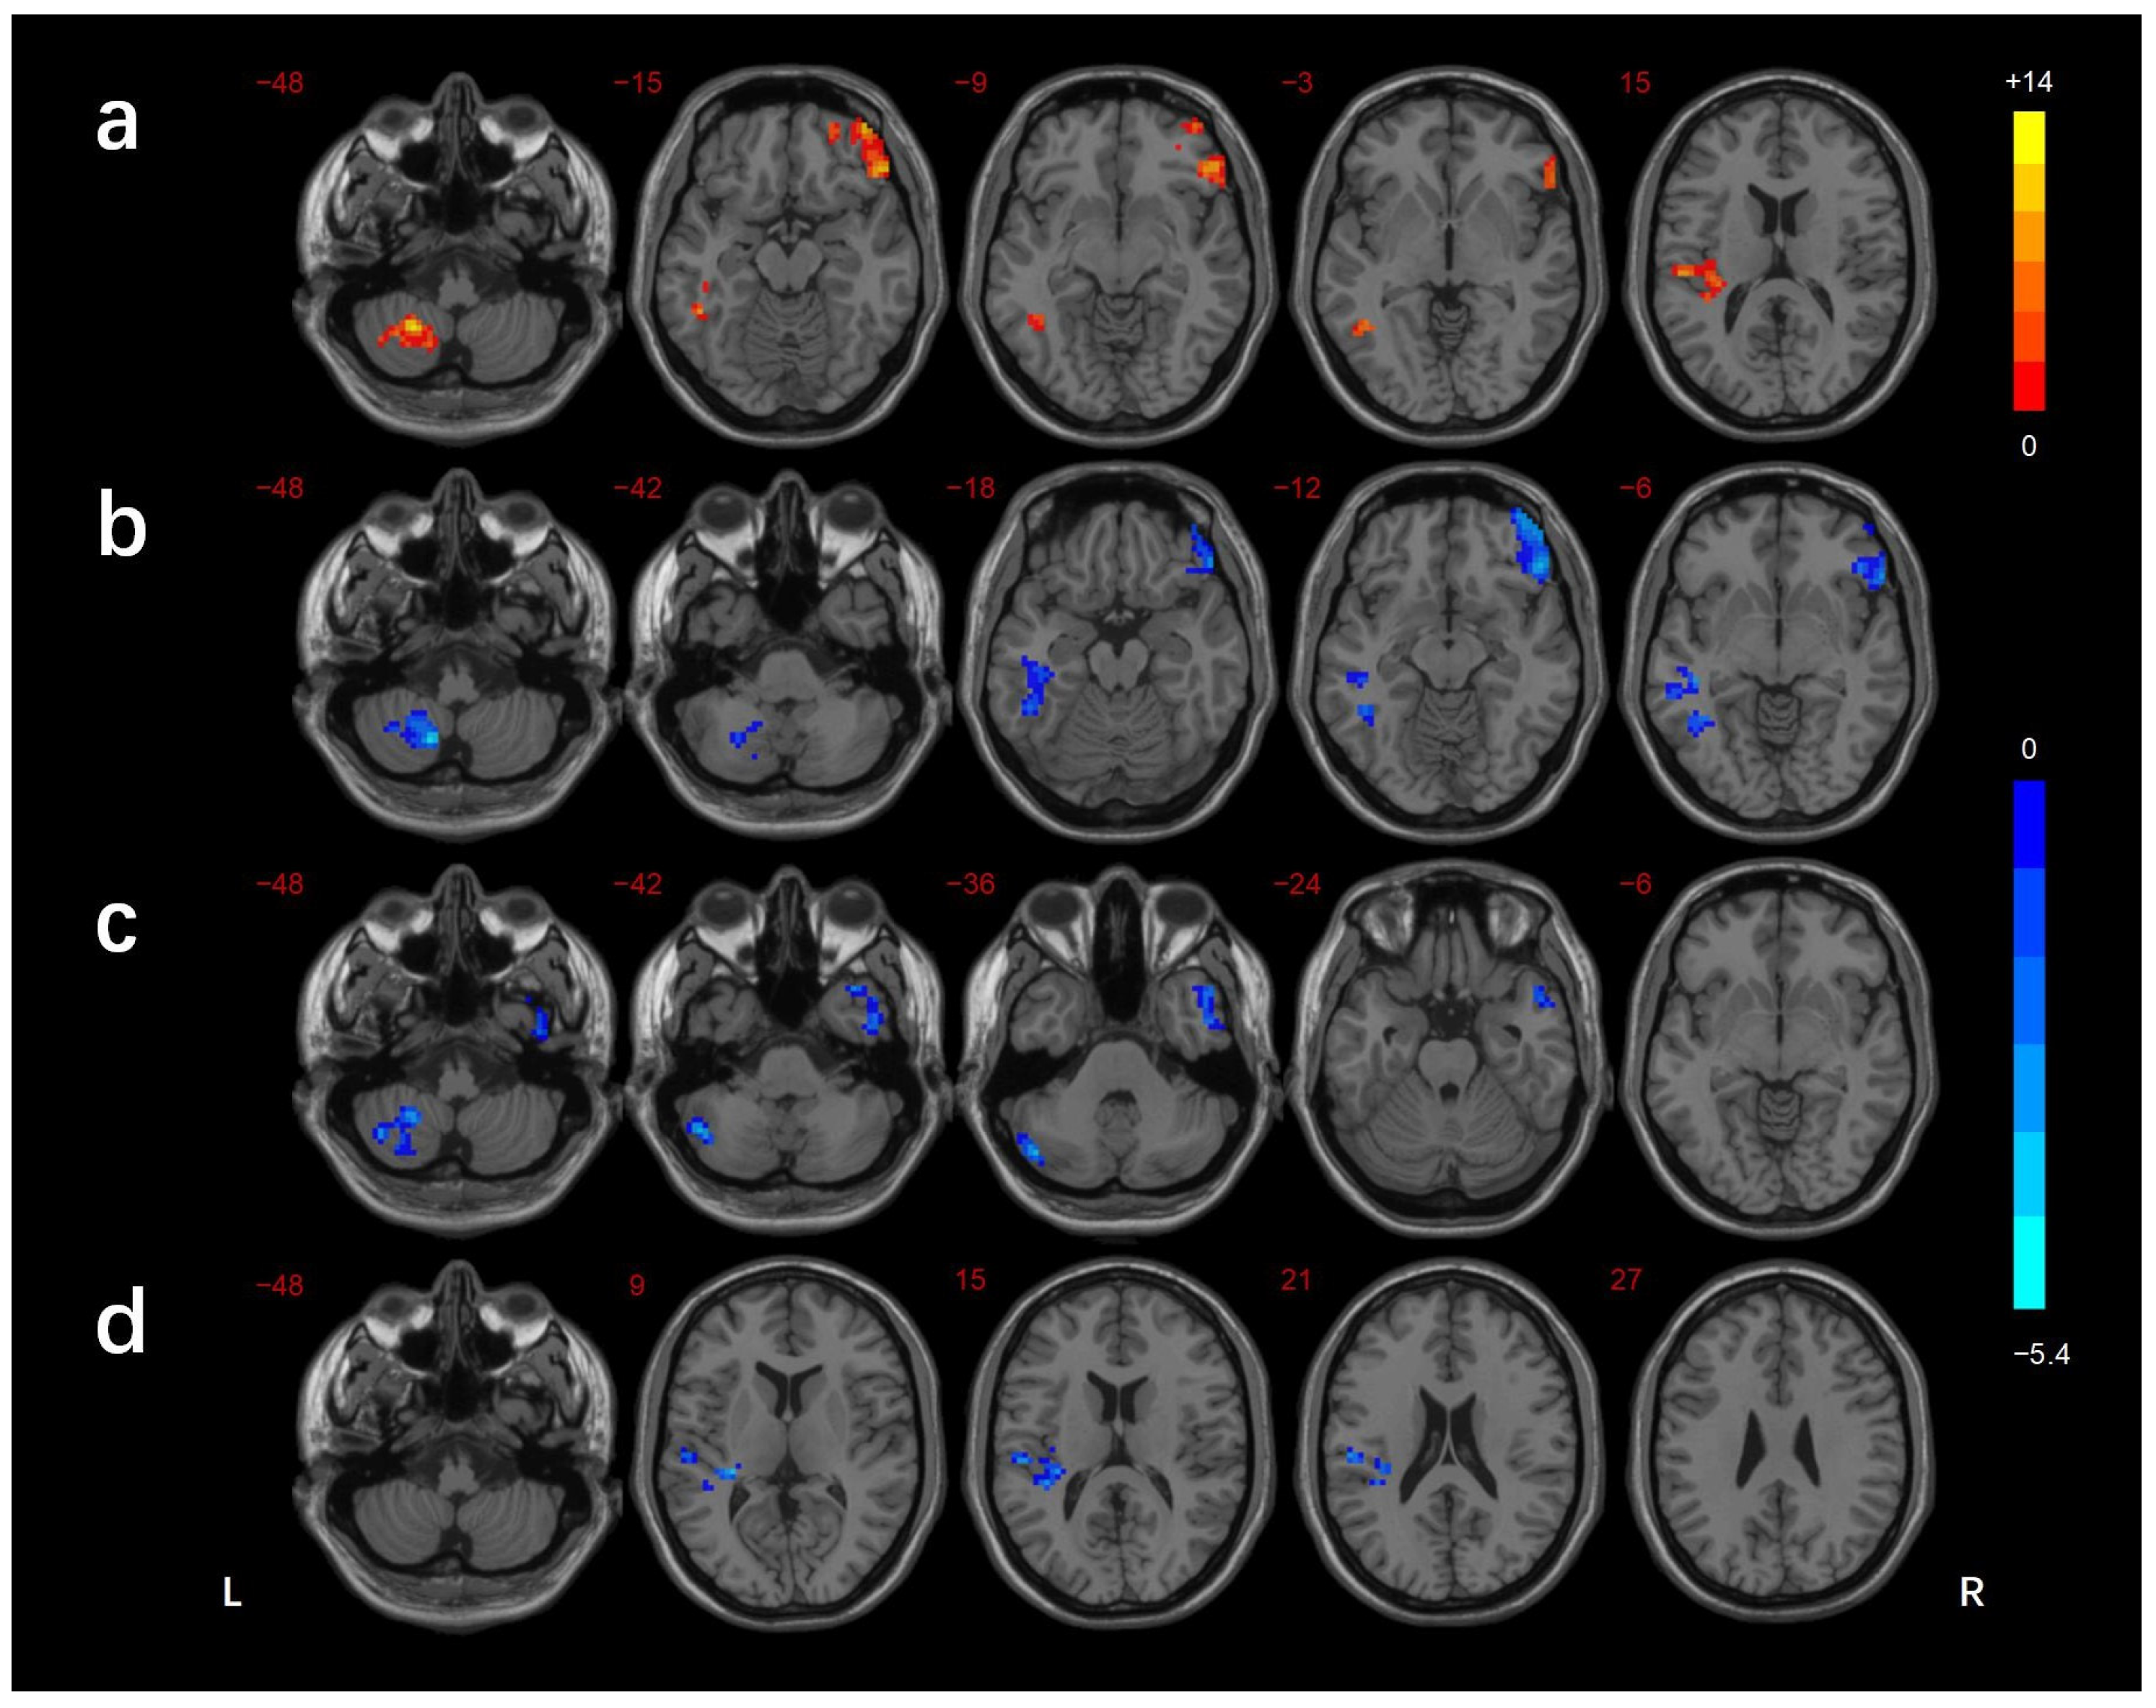

| Brain Regions | BA | Voxels (mm3) | Peak MNI Coordinates | f/t-Value | ||

|---|---|---|---|---|---|---|

| X | Y | Z | ||||

| ANOVA | ||||||

| L_cerebellar lobule VIII/Crus II | - | 104 | −24 | −54 | −48 | 13.916 |

| L_ITG/FG | 37 | 109 | −39 | −51 | −6 | 12.070 |

| R_IFG | 47 | 217 | 51 | 33 | −12 | 13.389 |

| L_STG | 13/41 | 116 | −36 | −30 | 9 | 12.689 |

| DMCN vs. HC | ||||||

| L_cerebellar lobule VIII/Crus I/II | - | 159 | −48 | −72 | −33 | −4.836 |

| R_ MTG/ITG | 38/21 | 175 | 51 | 12 | −30 | −4.089 |

| DMCI vs. HC | ||||||

| L_cerebellar lobule VIII | - | 125 | −15 | −63 | −48 | −5.304 |

| L_MTG/ITG/FG | 37 | 245 | −45 | −60 | 0 | −4.382 |

| R_IFG | 47 | 253 | 51 | 33 | −15 | −4.695 |

| DMCI vs. DMCN | ||||||

| L_STG | 41 | 124 | −30 | −30 | 9 | −3.784 |